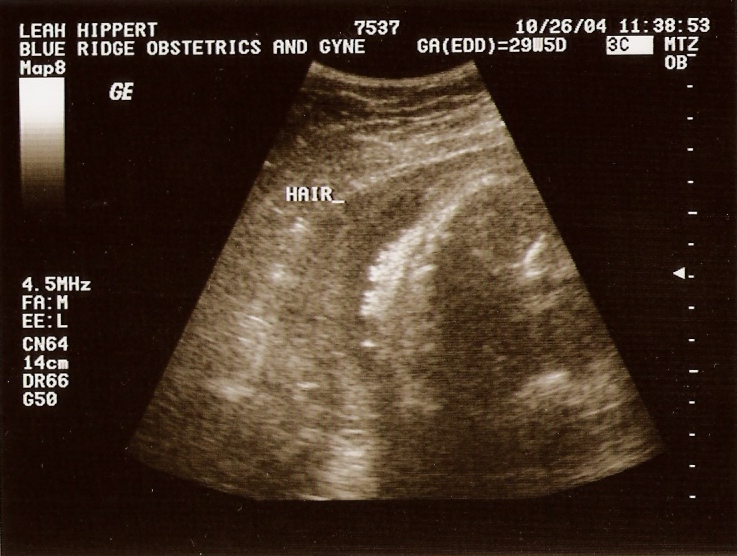

Taken On October26th 2004   Taken On October26th 2004   Taken On October26th 2004